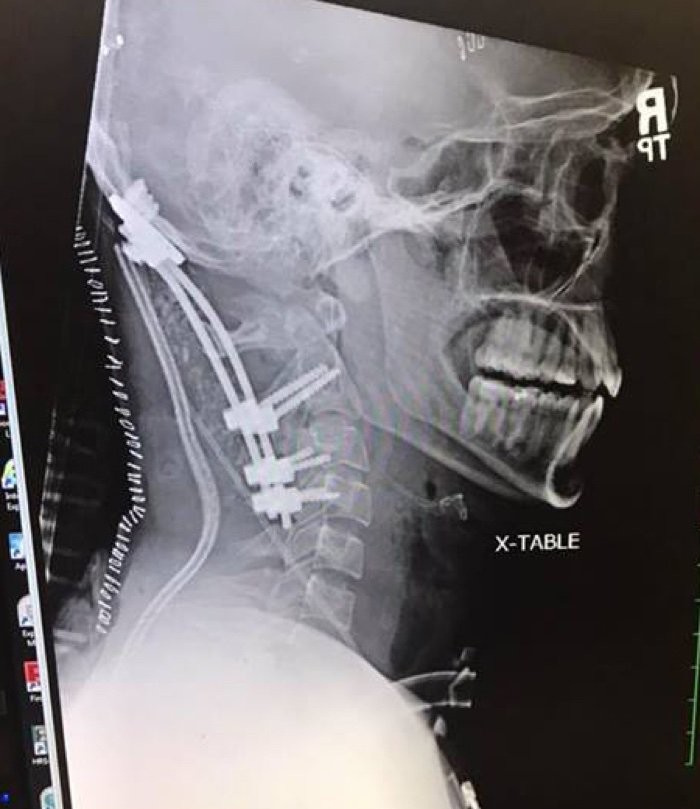

Тем не менее после того, как прошло критическое время, когда пациент уже должен был умереть, он всё ещё оставался жив. Было решено провести сложнейшую операцию. Хирурги сумели разместить в шее пластины, стержни и спинальные винты и стали надеяться, что всё это было не зря. Брук доказал, что не зря! Всё срослось, и постепенно Брук пошёл на поправку. Далее его ждал длительный курс реабилитации. Прошло 1,5 года, и парень уже может немного двигать шеей. Источник